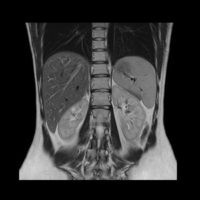

RMN Abdominal

Examinarea RMN abdominal

Poate depista diferite afectari ale organelor de la acest nivel:

ficat,

colecist,

pancreas,

splina,

glande suprarenale,

rinichi,

putand vizualiza prezenta tumorilor, a proceselor infectioase, a obstacolelor cailor biliare sau urinare.